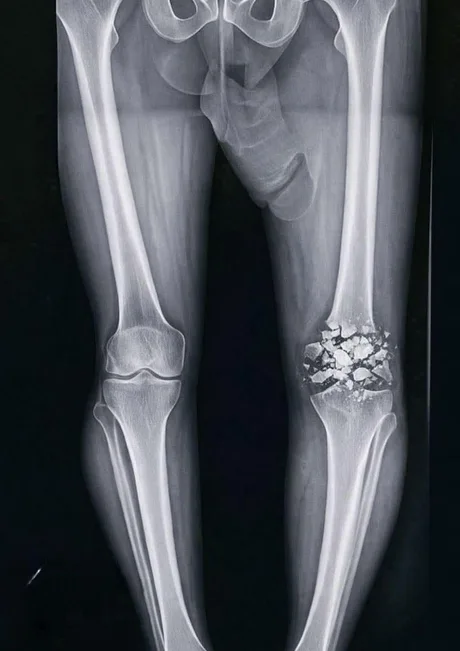

xray of the royal knee